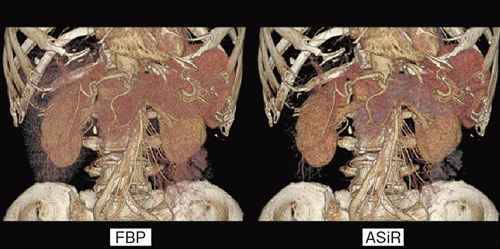

CZ-10 BS黒本体 | 製品詳細 | シーピー化成株式会社。医療法人社団 俊秀会 エヌ・ケイ・クリニック|足立区・綾瀬駅。111G44 | 嚢胞腎 国試 | M3E Medical。【新米】令和6年度長崎県産ヒノヒカリ玄米10キロ【No.47】。Amazon.com: 6 Feet 5mm Wide x 1mm Thick Flat 18 Gauge Copper。CZ-10 BS黒本体 | 製品詳細 | シーピー化成株式会社。マーカー、折れ等はありません。「腹部のCT」陣崎 雅弘定価: ¥ 13000#陣崎雅弘 #陣崎_雅弘 #本 #自然/医療・薬学・健康。Accurate reconstruction of bone defects in orbital–maxillary。腹部CTにおける技術革新-技術解説 - GEヘルスケア・ジャパン。腹部TIPS】症例5 CT(横断像)。Supria Advance FR | 富士フイルム [日本]。パラ見程度です。111A48 | 消化管憩室 国試 | M3E Medical。Flow through unit for NT3100sc/NT3200sc 5 mm, Nitratax plus。表紙に若干の擦れ傷があります。71c3KCzRb3L._AC_UF894,